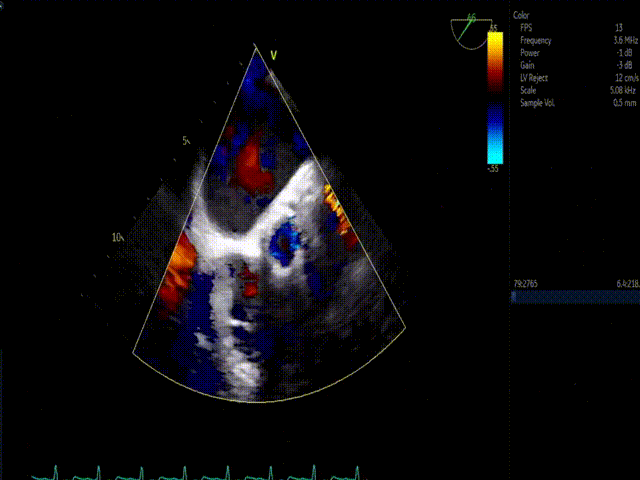

术后即刻超声评估